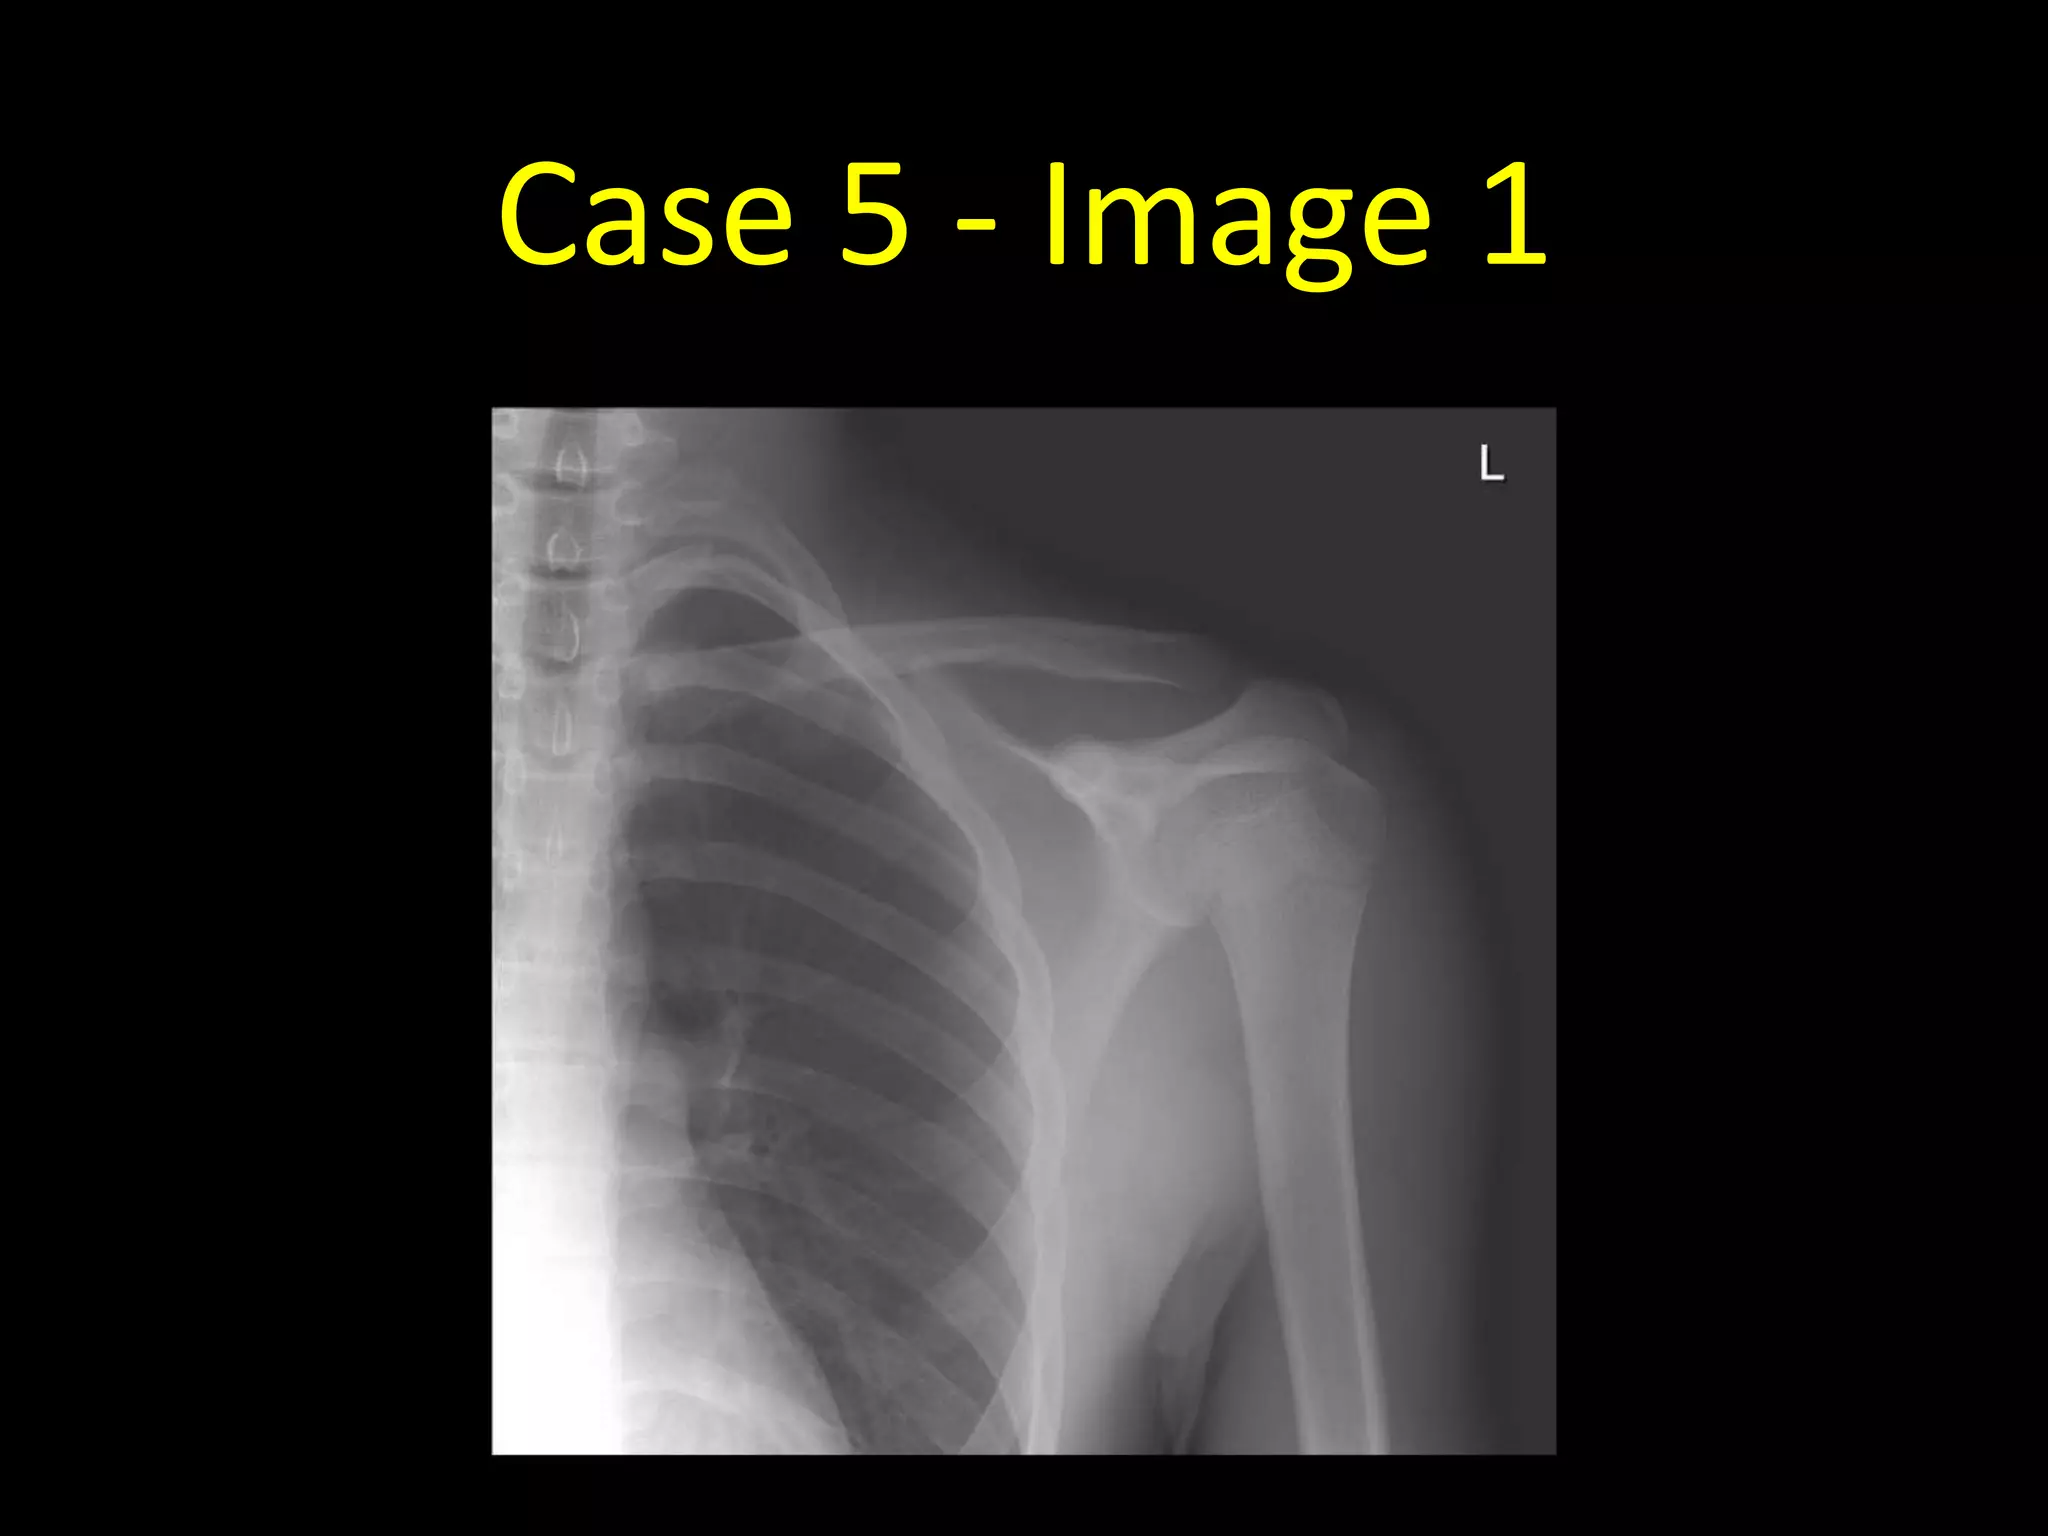

Case 5

• 15 year old with pain in the left shoulder after a fall

Case 5 - Image 1

Case 5 - Image 2

• Normal radiographs!

• Don’t be fooled by the left proximal

humeral growth plate (arrows)

• There appear to be two lines through

the left proximal humerus as the growth

plate runs obliquely through the plane

of the radiograph

• Note there are also growth plates visible

at the acromion and coracoid processes

• Remember in young patients to consider

if what you’re looking at might be a

growth plate